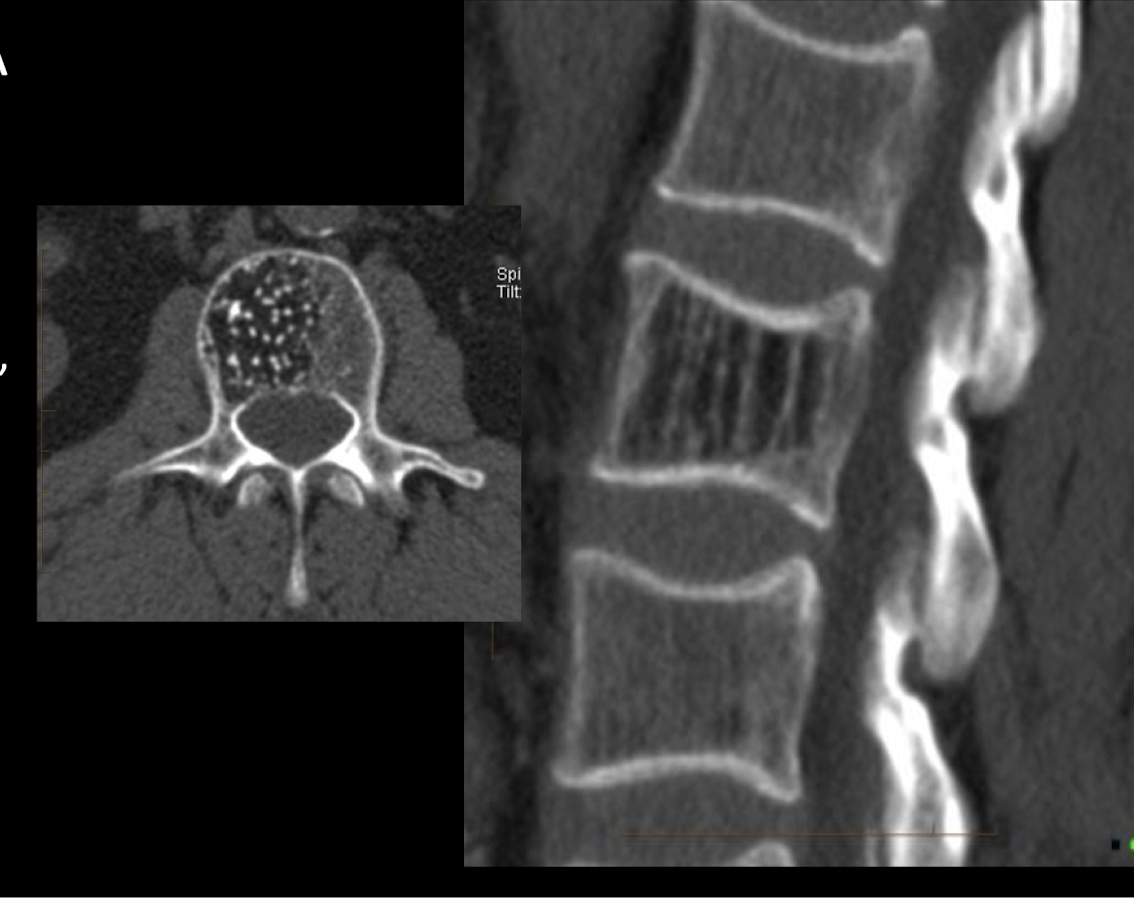

TC

A

lesion hipodensa

lunares o sal y pimienta en axial

tela de pana o barrotes en sagital